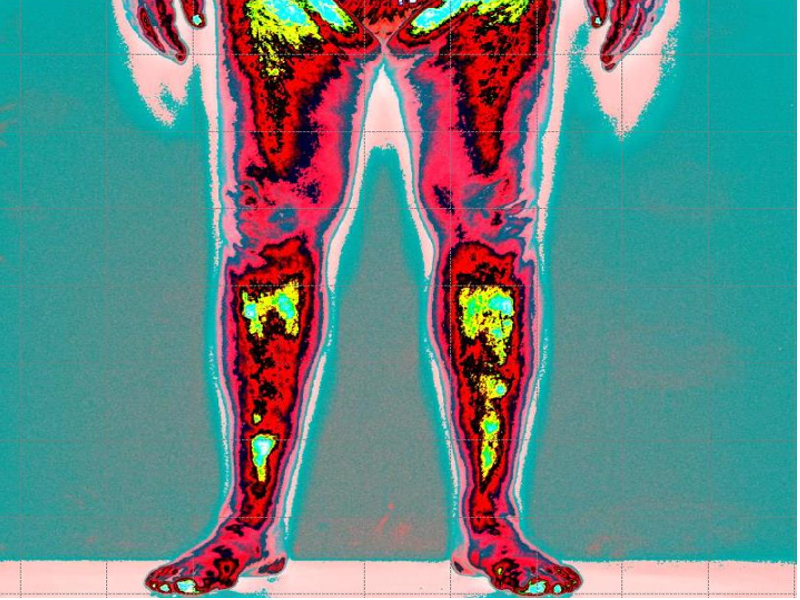

In questa immagine possiamo vedere il cliente paziente con lombalgia acuta causa discopatie multiple

Prime foto maggior tensione globale della muscolatura anteriore (colore blu scuro)

Leggenda: colore rosso inattivazione tensione muscolare

Verde, minima tensione muscolare

Azzurro normale tensione muscolare

Blu scuro, aumento della tensione muscolare